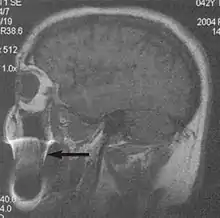

Flow can manifest as either an altered intravascular signal (flow enhancement or flow-related signal loss), or as flow-related artifacts (ghost images or spatial misregistration). Flow enhancement, also known as inflow effect, is caused by fully magnetised protons entering the imaged slice while the stationary protons have not fully regained their magnetization.[1] The fully magnetized protons yield a high signal in comparison with the rest of the surroundings. High velocity flow causes the protons entering the image to be removed from it by the time the 180-degree pulse is administered. The effect is that these protons do not contribute to the echo and are registered as a signal void or flow-related signal loss (Fig. 2).[1] Spatial misregistration manifests as displacement of an intravascular signal owing to position encoding of a voxel in the phase direction preceding frequency encoding by time TE/2.The intensity of the artifact is dependent on the signal intensity from the vessel, and is less apparent with increased TE.[1]